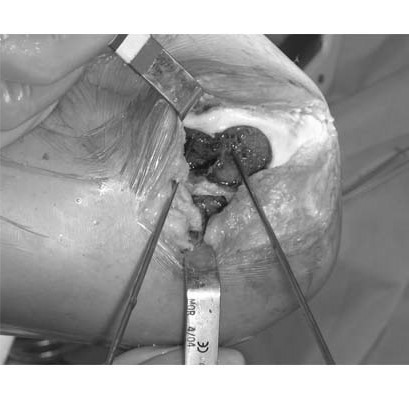

4.Due to the location of the lesion, an open mosaicplasty with one plug is selected as our treatment choice. The harvesting tool is placed within the lesion removing the plug with the damaged cartilage. On the image on the right, the inside of the recipient site is inspected with the arthroscope.

5.In the image to the left, the donor plug (left plug) and recipient plug (right plug) are placed next to each other demonstrating the degree of damage in the recipient site. The image on the right shows the donor plug after being placed flush with the recipient cartilage into the recipient site.

5.Both recipient sites (A & B) are treated with precisely contoured grafts covered with healthy cartilage that are removed from a fresh allograft distal femur using specialized instrumentation.